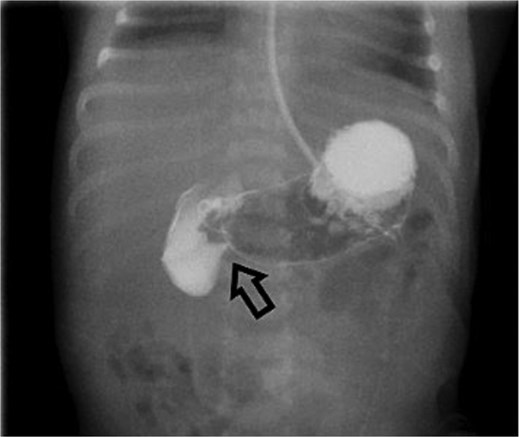

On Day 3 of life, she developed multiple episodes of bilious emesis and passed meconium-stained stools. An abdominal radiograph revealed gas-filled, non-distended bowel loops on the right and absence of small bowel gas on the left (Fig. 1), raising suspicion for malrotation. An upper GI (UGI) series confirmed abnormal duodenal positioning and obstruction, suggestive of malrotation with volvulus (Fig. 2). Emergent Ladd’s procedure was performed, revealing midgut volvulus with cloudy peritoneal fluid but viable bowel.

Initial UGI series demonstrates abnormally dilated descending duodenum with no contrast crossing the midline. Findings are consistent with obstruction.